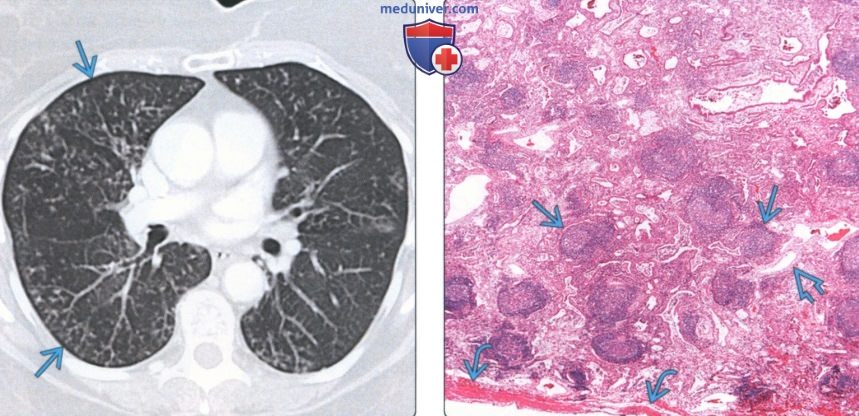

КТ ретроперитонеального фиброза: Изображения и диагностика